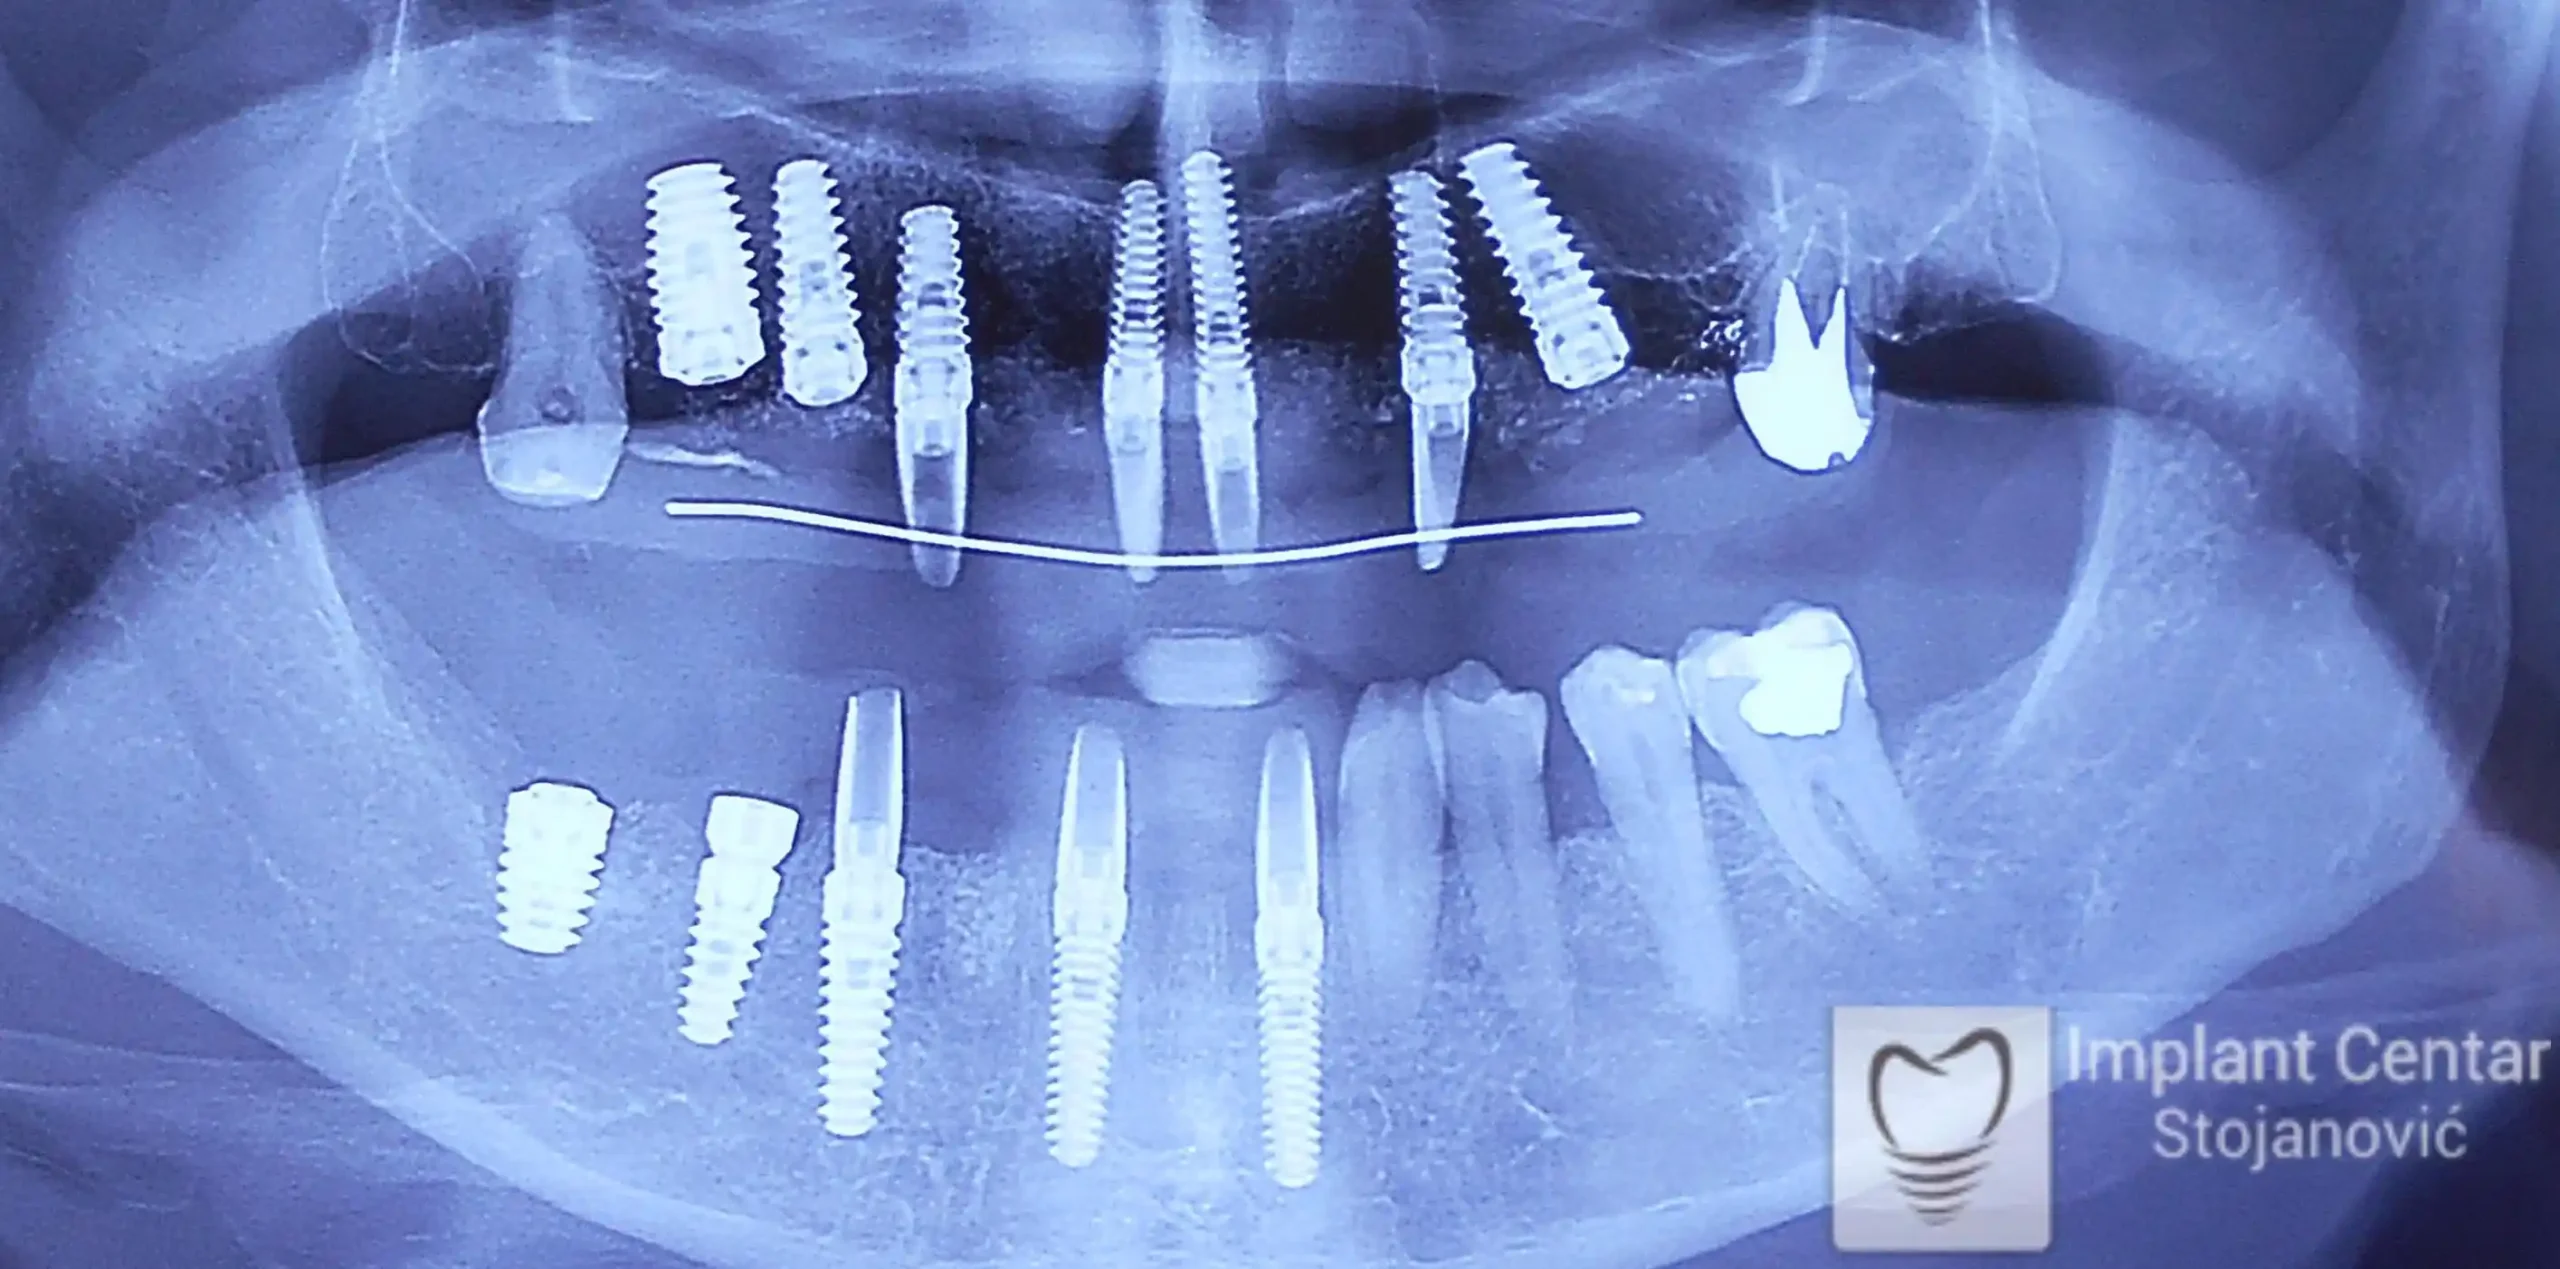

Zbog toga je plan terapije uključivao vađenje svih preostalih zuba i ugradnju implantata u gornjoj i donjoj vilici. U gornjoj vilici postavljena su i dva tuberopterigoidna implantata, kao zamena za sinus lift proceduru, što se može videti na ortopan snimku nurađenom odmah nakon ugradnje (slika 3).

Nakon vađenja zuba, ugrađeni su implantati. Na slici 3 prikazan je ortopan snimak sa ugrđenim implantatima. Tokom perioda osteointegracije, pacijent je bio zbrinut fiksnim privremenim krunicama na implantatima, koje su izrađene samo dva dana nakon hirurške intervencije.